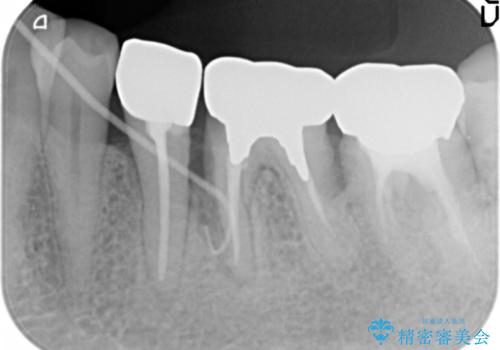

精査したところ奥歯(左下6)が破折しており、保存不可能と診断されました。

保存不可能な奥歯(左下6)を抜歯し、機能していない親知らず(左下8)の移植を行いました。

移植後、生着を待って根管治療及び補綴修復を行いました。